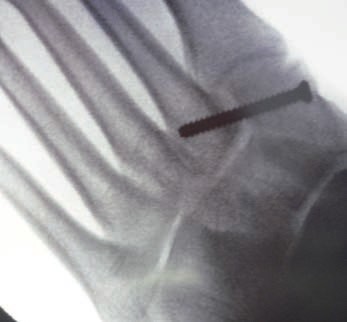

Patienten mit Verletzungen Grad II und III (n. Nunley) profitieren von einer operativen The rapie 31. Bei frischen Verletzungen gelingt meist die geschlossene Reposition durch eine Repositionszange unter Bildverstärkerkontrolle. Anschließend wird über eine kleine mediale Inzision ein Kirschnerdraht vom Os cuneiforme mediale in die MetatarsaleII-Basis gebohrt und das Lisfranc-Ligament durch eine Stellschraube in anatomischer Stellung ruhiggestellt. Durch weitere Schrauben lässt sich bei Bedarf das Tarsometatarsale-I-Gelenk und der Raum zwischen Os cuneiforme I und II stabilisieren. Nach Lagekontrolle unter dem Bildverstärker wird eine durchbohrte Schraube mit durchgehendem Gewinde eingebracht (Abb. 7). Werden Zugschrauben verwendet, kommt es zu einer unphysiologischen Kompression der Gelenkfiächen.

Kanülierte Schrauben erleichtern das Vorgehen, wobei grundsätzlich auch Standard-Kleinfragmentschrauben verwendet werden können. Die in der Literatur beschriebene Verwendung von 2,0‑mm-Kirschnerdrähten hat sich bei den Verfassern nicht bewährt. Hier besteht ein erhebliches Risiko der Lockerung und Dislokation 32. Thordarson und Hurvitz (2002) 33 berichten über den Einsatz von resorbierbaren Schrauben, Hu et al. (2014) sowie Hsu et al. (2015) über den Einsatz einer das Tarsometatarsale-I-Gelenk überspannenden Platte 34 35.

Gelingt die geschlossene Reposition nicht, was insbesondere bei verzögerter Diagnostik der Verletzung aufgrund der ausgeprägten Narbenbildung zwischen dem I. und II. Strahl der Fall sein kann, so wird über einen dorsalen Zugang direkt über dem Lisfranc-Ligament das Narbengewebe ausgeräumt und anschließend nach Reposition die Stellschraube gesetzt.